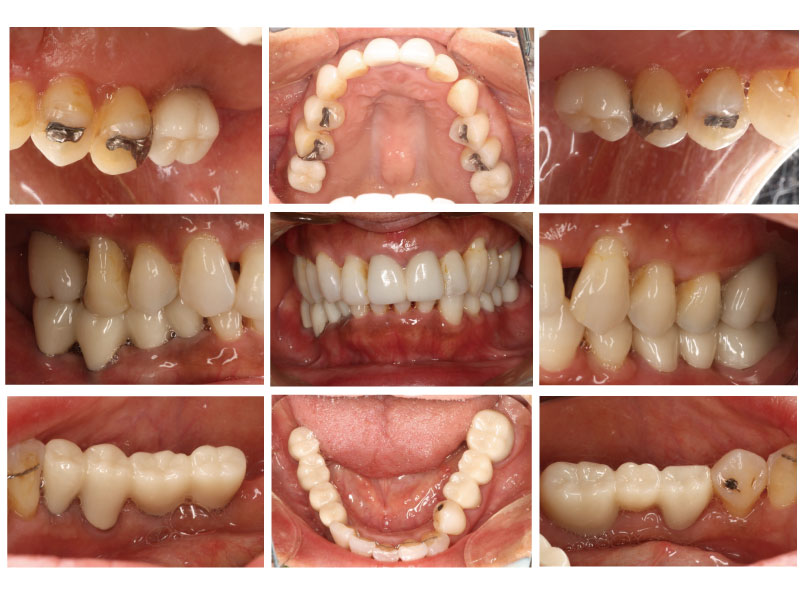

初診時口腔内写真

治療終了時口腔内写真